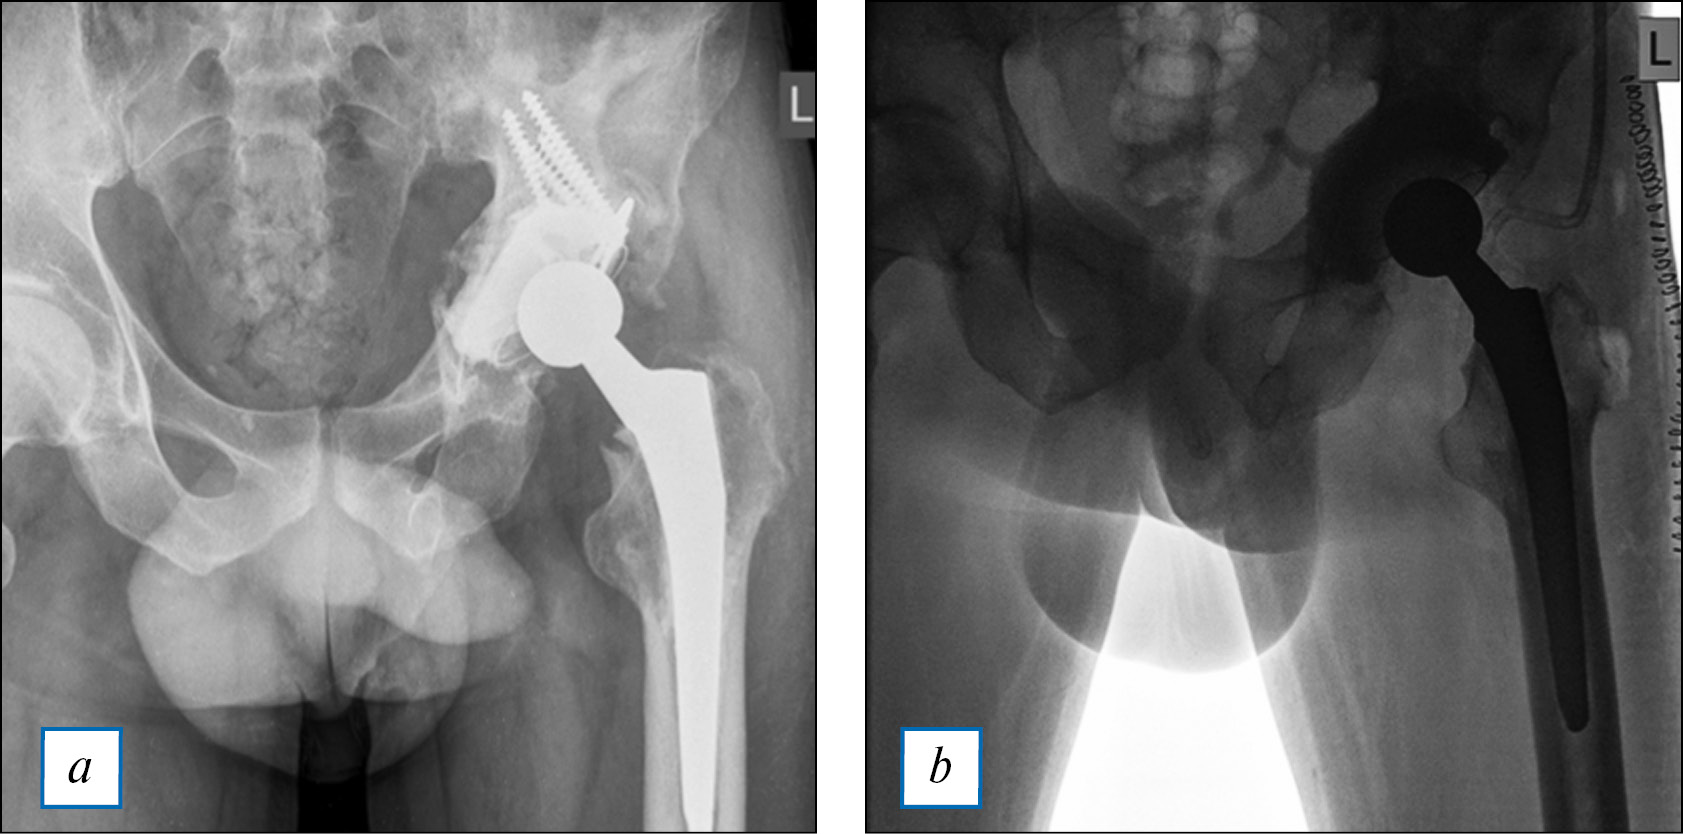

С помощью 3DP в травматологии и ортопедии создаются индивидуальные имплантаты из титана и костнозамещающего материала, благодаря которым появилась возможность замещения любых по форме, сложности и размерам костных дефектов. Для их создания необходимы только данные МСКТ-обследования пациента [2, 14]. Одним из перспективных направлений использования аддитивных технологий 3DР является создание гибридных эндопротезов, включающих титановый и костнозамещающий компоненты (рис. 6). Кроме синтетических материалов в качестве костнозамещающего вещества возможно использовать алло- и аутокость. В настоящее время уже разработаны технологии изготовления гибридных эндопротезов тазобедренного, коленного, плечевого и лучезапястного суставов [22, 59]. Проведенные исследования статистически достоверно доказали их эффективность, в том числе при лечении пациентов с перипротезной инфекцией. По данным оценки клинико-рентгенологических послеоперационных результатов не выявлено ни одного случая рецидива периимплантной инфекции, а также развития неинфекционных осложнений, включая вывихи, миграцию компонентов эндопротеза, переломы костнозамещающего компонента имплантата. После операции полностью отказались от приема обезболивающих препаратов 73% (n=11) пациентов. Все больные после эндопротезирования тазобедренного и коленного суставов могли передвигаться с помощью костылей с частичной опорой на оперированную конечность. У всех пациентов после ревизионного эндопротезирования плечевого сустава сохранились движения в нем. Использование индивидуальных гибридных эндопротезов в ревизионном эндопротезировании крупных суставов позволило не только купировать инфекционный процесс, сохранить функцию опоры и передвижения, артикуляцию, но и прецизионно заместить дефекты костной ткани [59].

Рис. 6. Рентгенограмма таза: a — септическая нестабильность эндопротеза левого тазобедренного сустава, b — рентгенограмма после ревизионного эндопротезирования с имплантацией индивидуального спейсера, изготовленного с помощью 3DР (данные Р.О. Горбатова).

Fig. 6. Pelvic radiographs: a — Septic instability of an endoprosthesis of the left hip joint; b — Same patient, revision endoprosthesis with implantation of an individual spacer fabricated using 3DP (Data of Gorbatov R.O.).